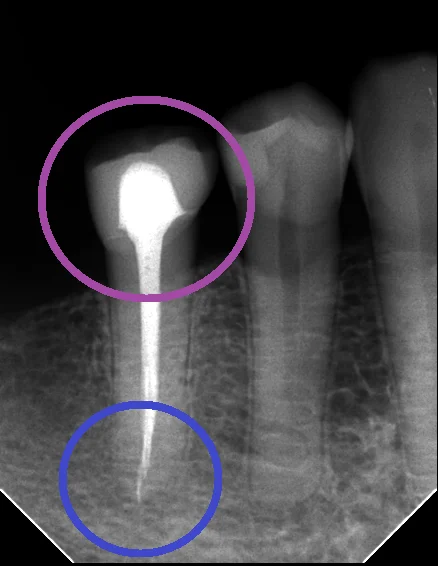

もうほとんど歯が残っていない状況にも関わらず、無理やりレジンで治療をされています。

(紫の丸の部分)

当然強度が足らないわけですから、複数箇所に亀裂が入っており、至る所が虫歯になってしまっています。

ちなみに、この神経の治療も、根の先の方に器具が折れて入り込んでしまっています。(赤い丸の部分)

今回のケースでは根の先にそこそこなサイズの膿が溜まっている様子(青い丸の部分)